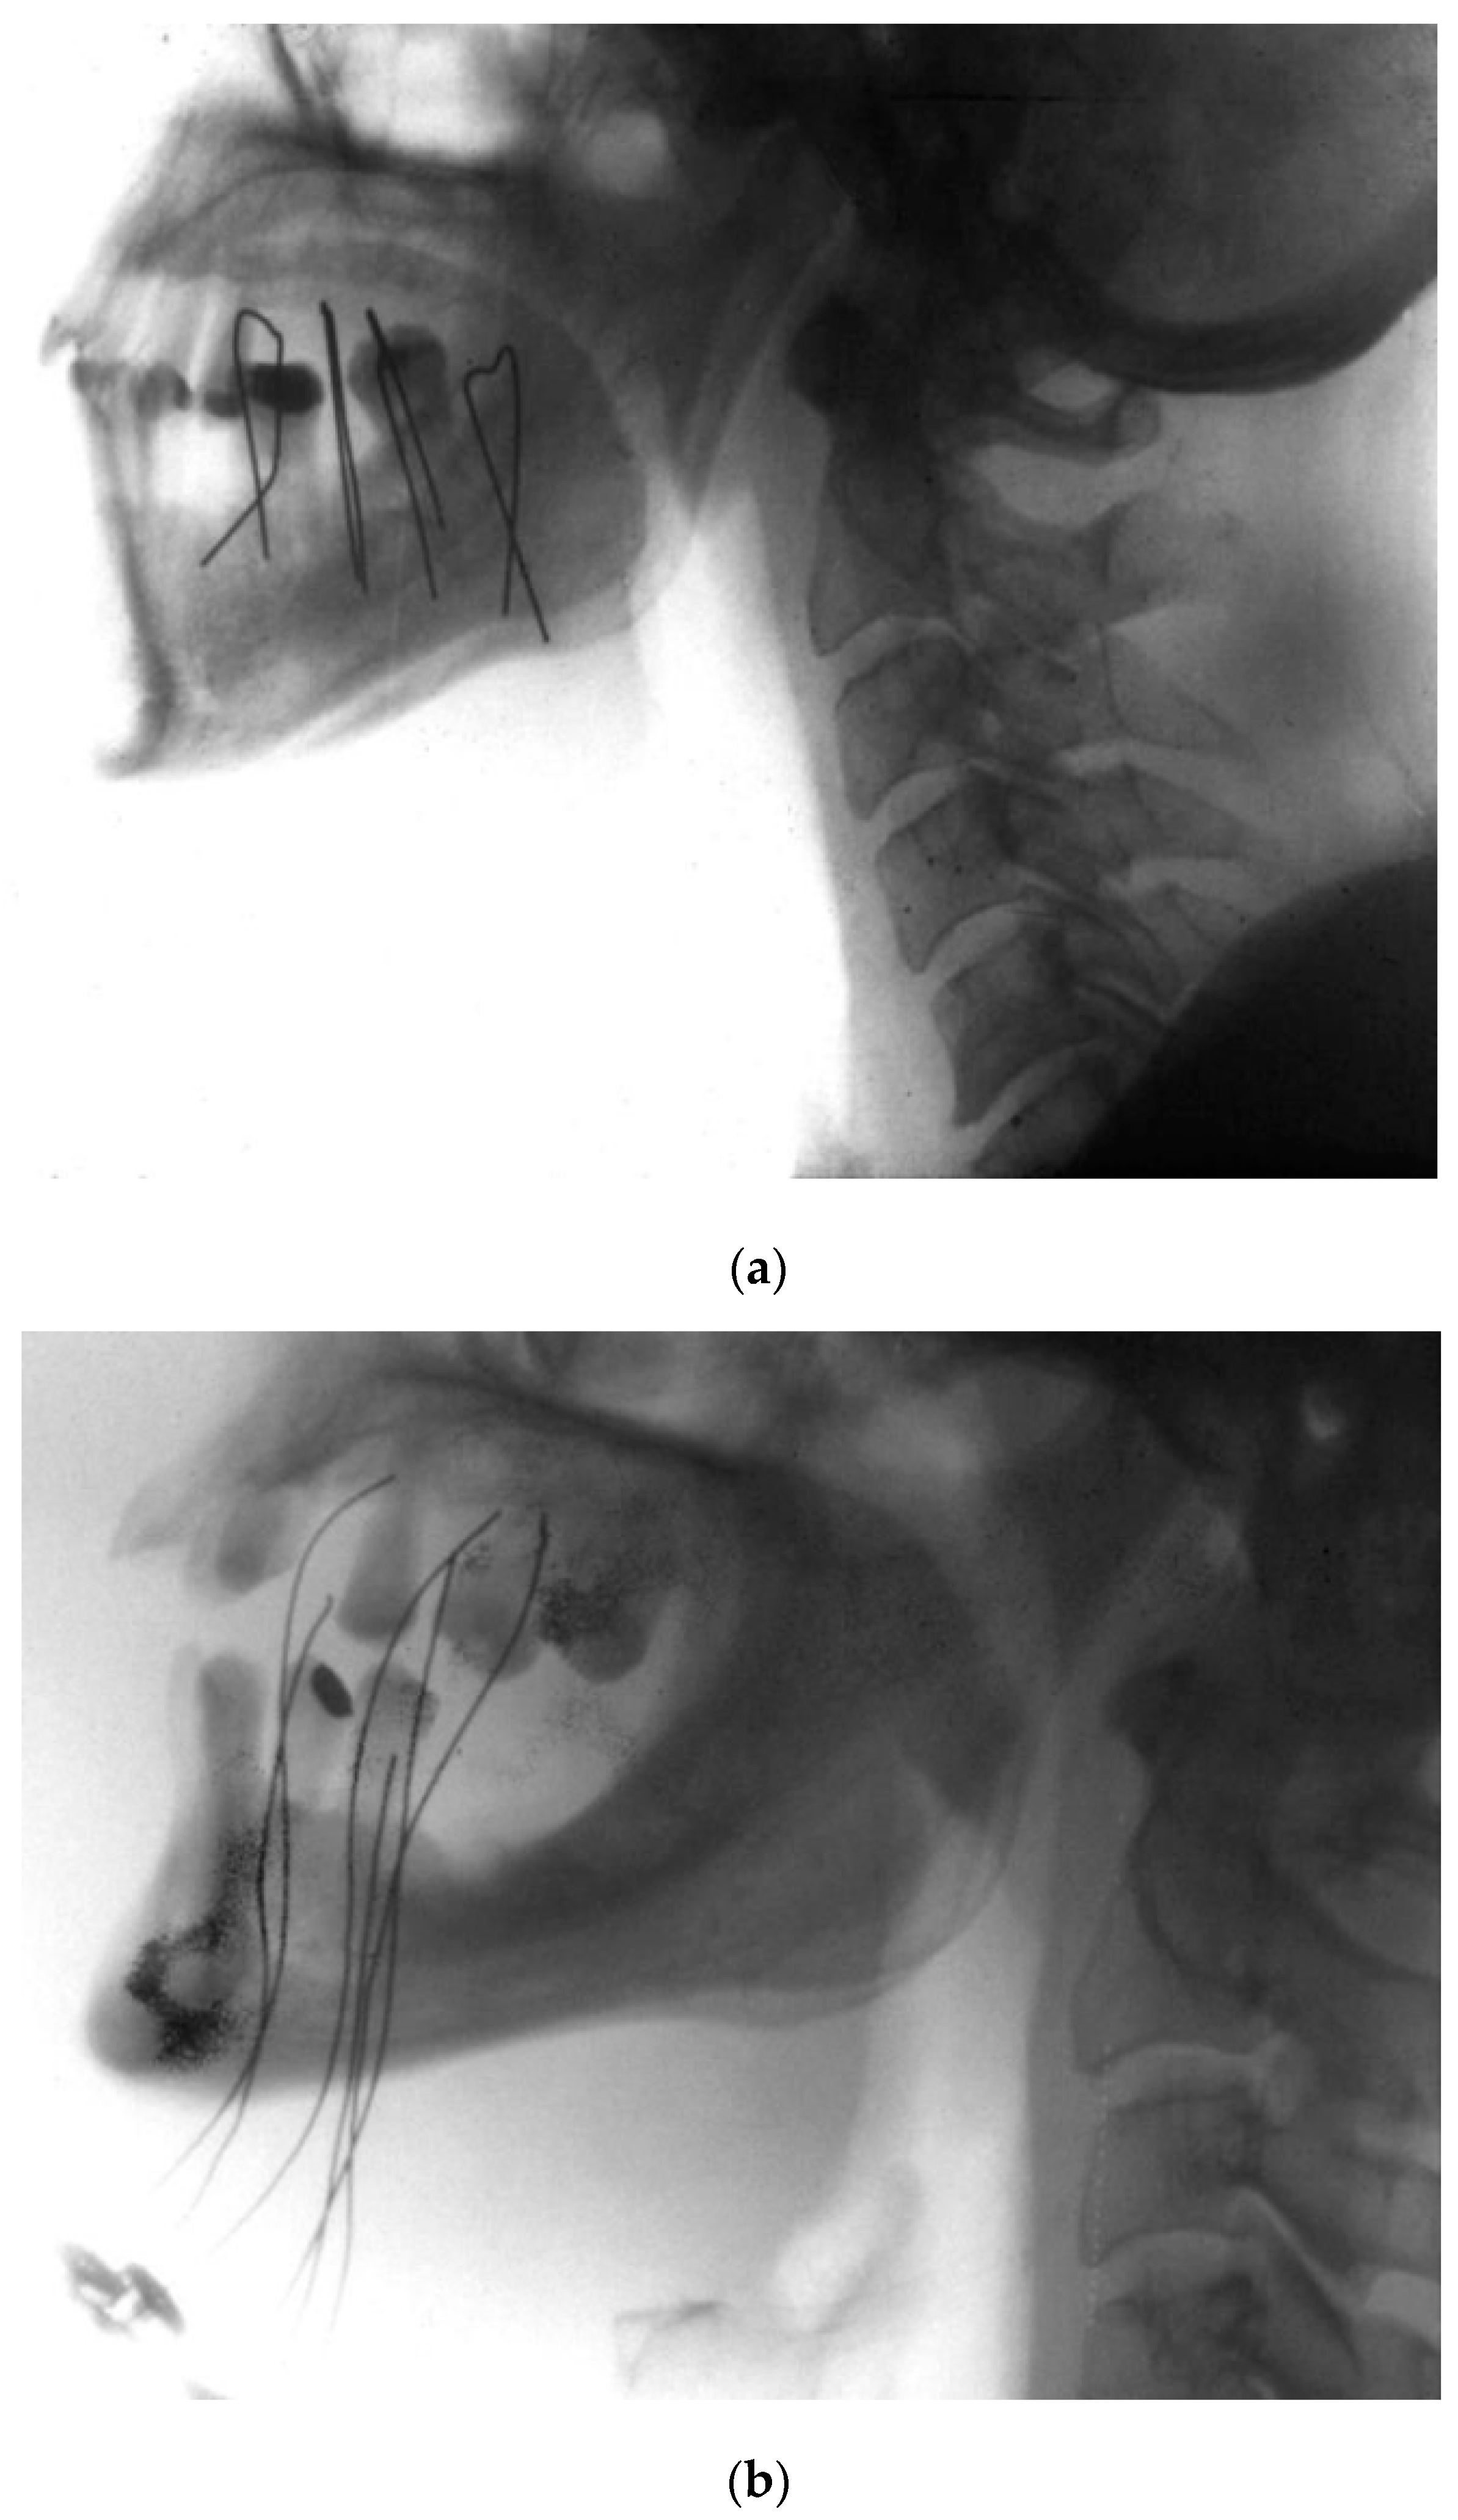

- Kovács, G.; Martinez-Monge, R.; Budrukkar, A.; Guinot, J.L.; Johansson, B.; Strnad, V.; Skowronek, J.; Rovirosa, A.; Siebert, F.A.; GEC-ESTRO Head & Neck Working Group. GEC-ESTRO ACROP recommendations for head & neck brachytherapy in squamous cell carcinomas: 1st update—Improvement by cross sectional imaging based treatment planning and stepping source technology. Radiother. Oncol. 2017, 122, 248–254. [Google Scholar] [CrossRef] [PubMed]